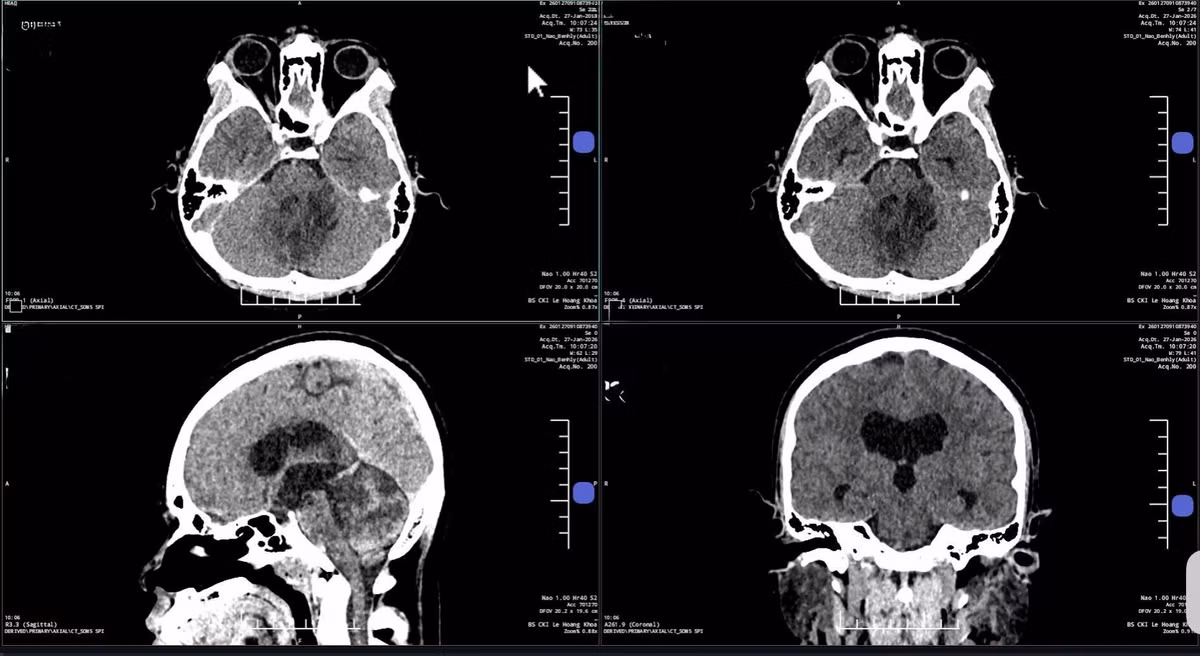

Ảnh MRI 3 Tesla cho thấy khối u nằm sâu vùng góc hành não của bà Hạnh - Ảnh BVCC

Hậu phẫu, bà Hạnh tỉnh táo, tiếp xúc tốt, hết đau đầu, lưỡi mềm và nói rõ hơn. Hình CT sọ não kiểm tra hậu phẫu cho thấy không chảy máu, không phù não, các cấu trúc vùng hố sau ổn định. Dây thần kinh số 12 bị chèn ép trước mổ vẫn nguyên vẹn, chưa có dấu hiệu tổn thương không hồi phục.